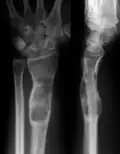

X-ray showing enchondromas localized in the lower part of the radius of a 37-year-old patient affected with Ollier disease -

MRI showing enchondromas localized in the lower part of the radius of a 37-year-old patient affected with Ollier disease -